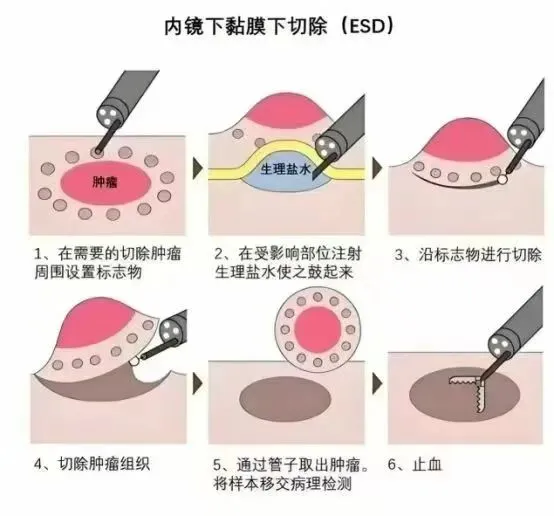

內鏡黏膜下剝離術(ESD)

什麽是ESD呢?

是指在內鏡的直視下(xià),使用高(gāo)頻電流發生器和黏膜切開(kāi)刀等器械,將黏膜病(bìng)變或黏膜下病變完整剝離的微創(chuàng)技術。主(zhǔ)要用於早期消化道腫瘤的治療,如早期食管癌、早期胃癌、間質瘤及結腸早期腫瘤等(děng)。對於符合條件的(de)早期消化道腫瘤,ESD能夠實現病灶的完整切(qiē)除,術後複發率低(dī),患者生活質量高。

與傳統外科手術相比(bǐ),ESD具有創傷小、恢複快、保(bǎo)留器官功能完整等優點(diǎn)。它能夠一次性徹底切除一定麵積的淺表病變(biàn),提高了治(zhì)愈率和降(jiàng)低了癌症複發率。